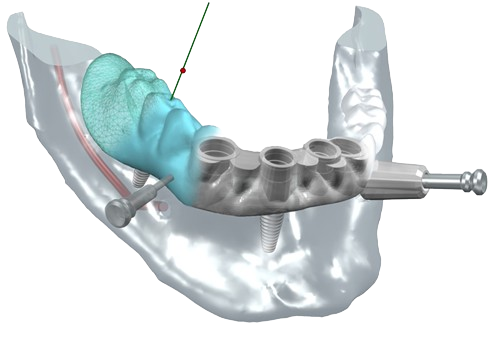

A partir de votre radio 3D réalisée au cabinet, nous lisons votre examen grace à des logiciels permettant une simulation précise du positionnement de vos implants dans l’os.

Cette vision 3D de l’implant dans l’os et en rapport avec les futures dents permet une reflexion « graftless », c’est a dire une implantologie nécessitant un minimum de greffe osseuse, donc plus rapide et moins mutilante.